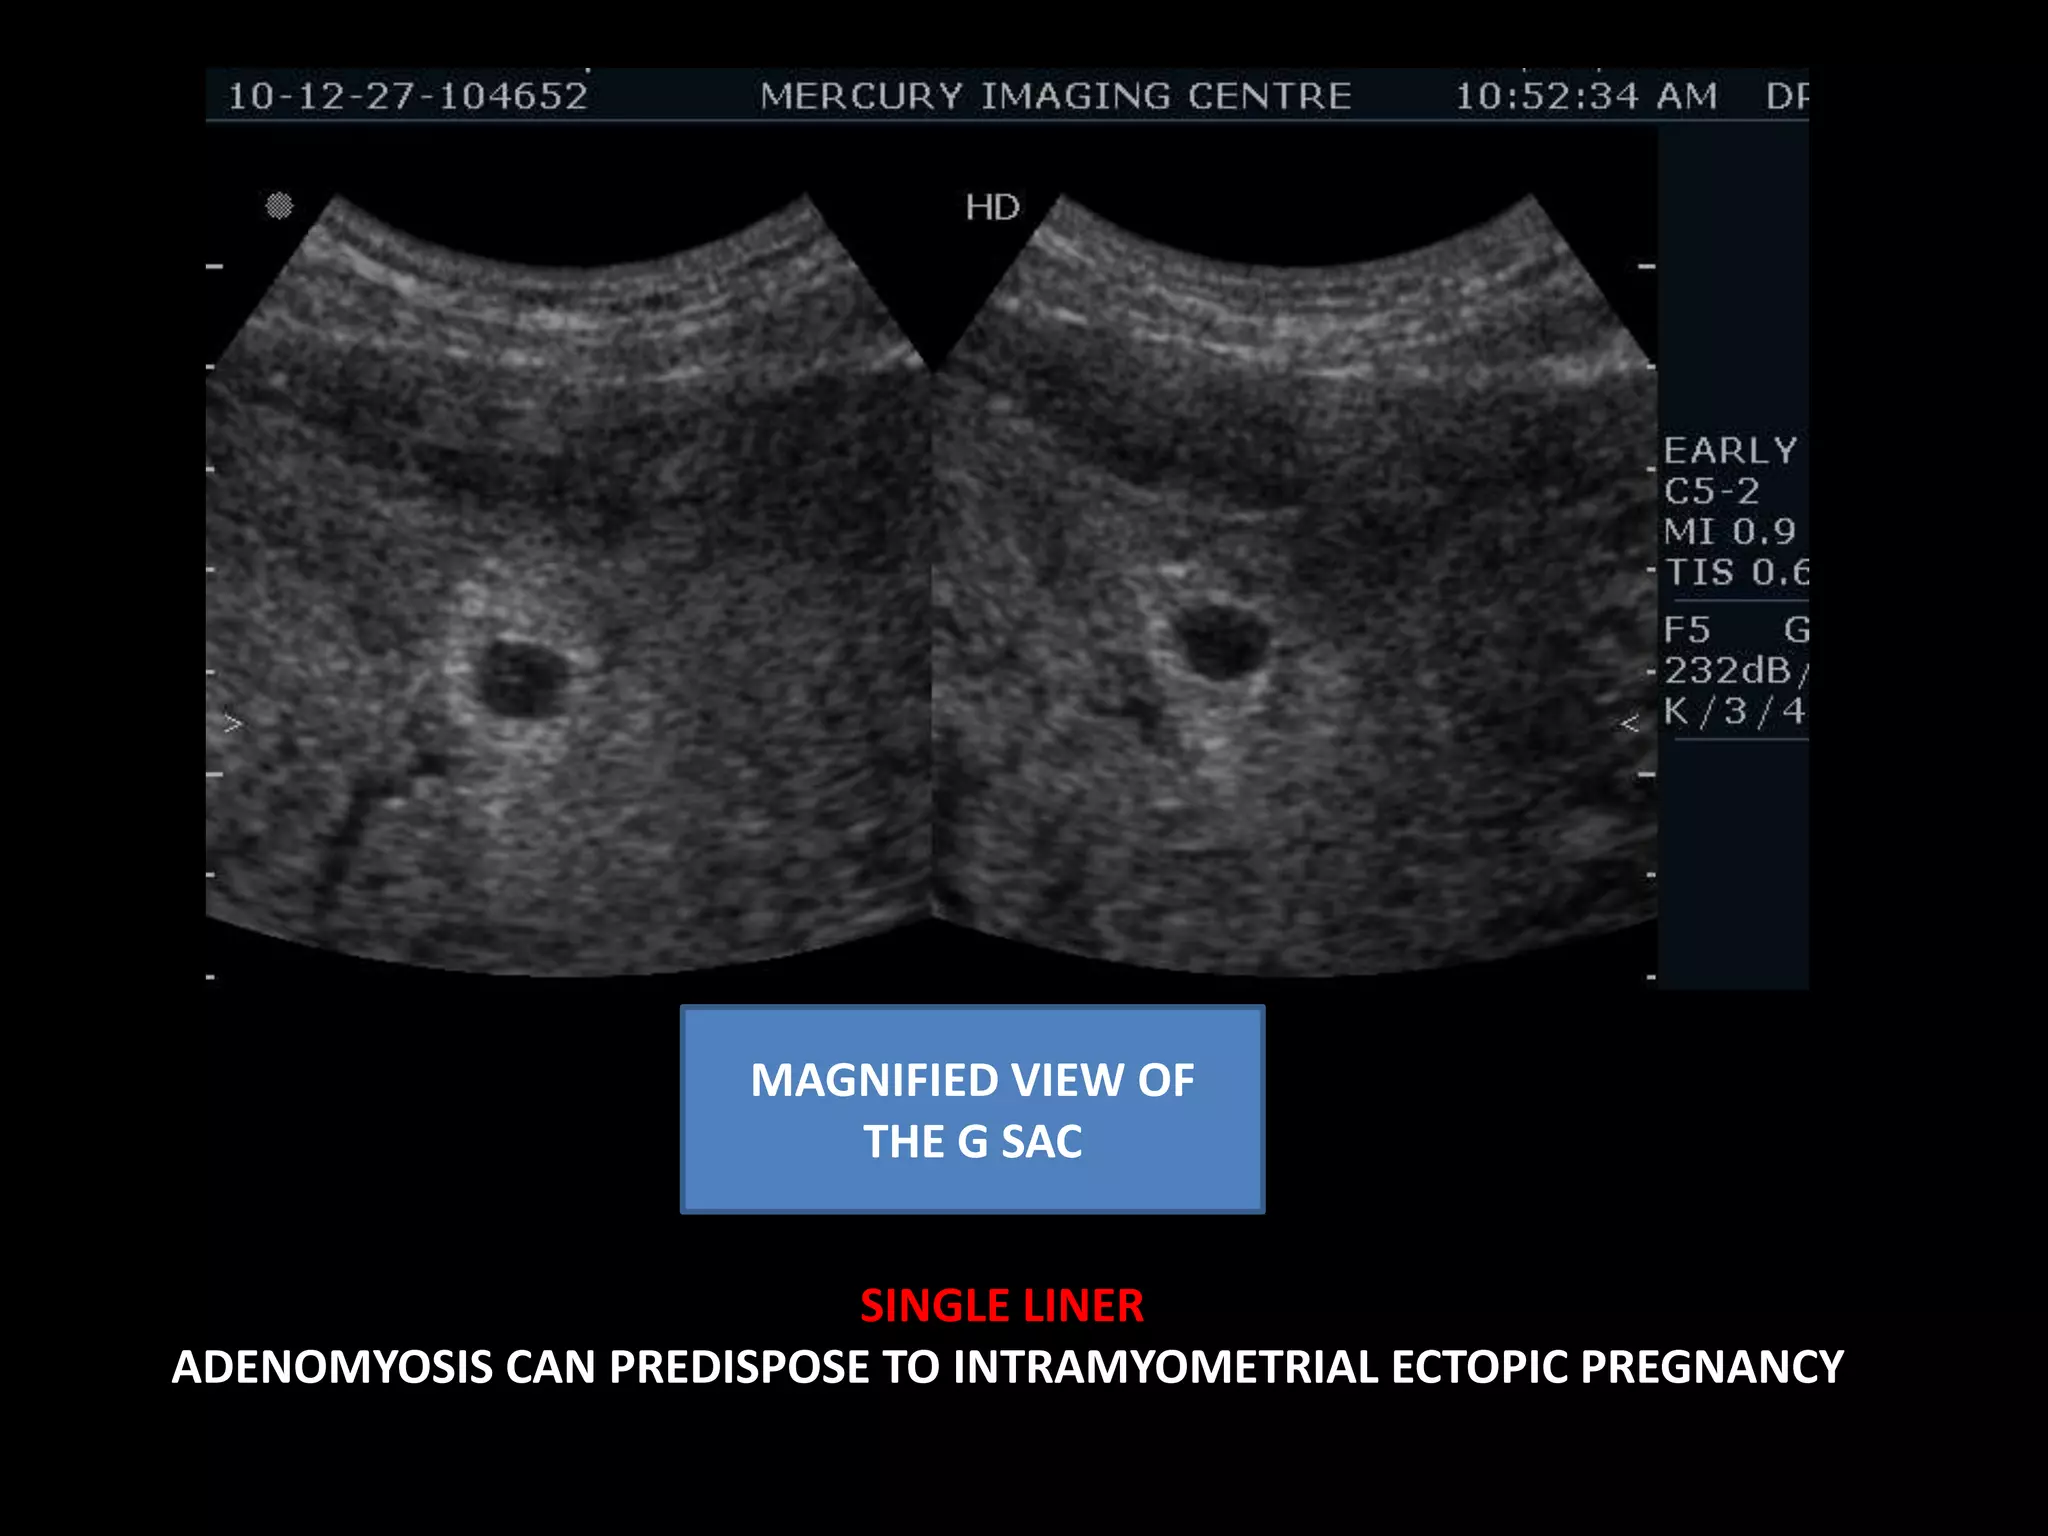

G SAC WITH NO FETAL NODE/ NO YOLK SAC. CORROBORATES WITH POG 5WKS ODAYS ......FOLLOW UP FOR VIABILITY  HETEROGENOUS  ECHOPATTERN OF THE MYOMETRIUM

MAGNIFIED VIEW OF THE G SAC  SINGLE LINER ADENOMYOSIS CAN PREDISPOSE TO INTRAMYOMETRIAL ECTOPIC PREGNANCY

MAGNIFIED VIEW OFTHE G SAC SINGLE LINER ADENOMYOSIS CAN PREDISPOSE TO INTRAMYOMETRIAL ECTOPIC PREGNANCY